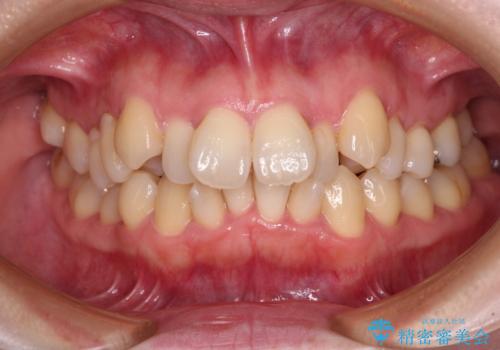

- 上下前歯のデコボコと、上顎の八重歯を気にして来院された患者様です。

下顎に対して上顎が前方にあり、第一大臼歯による咬合状態は上顎前突であったため、上顎のみ左右の第一小臼歯を抜歯し、ワイヤー装置にて矯正治療を行うこととしました。